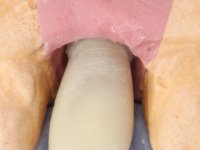

An impression was made on the implant with open tray technique using soft and regular consistency putty. At the laboratory, after confection of the work model, a diagnostic waxing was performed, which sought to find an aesthetic compromise solution. In this sense, a temporary workpiece screwed onto the implant was used to simulate the difficulties we would have with screwing the definitive work. This study abutment consisted of wax to reproduce soft and hard tissues, seeking to anticipate the use of ceramics of gingival and coronary shade. Also, part of the interproximal papillae corresponding to the distal portion of the 2.1 tooth and the mesial tooth of the tooth 2.3 were also waxed, anticipating the use of composite resin “chips” with gingival tonality. Finally, a veneer was waxed to correct the microdontia of the tooth 1.2. In this waxing, the vestibular emergence of the orifice for access to the screw of the implant abutment was evident. Once this therapeutic option was accepted, the implant abutment in polymerized composite resin was prepared at the lab, as well as the papillary "chips", also in composite resin of gingival tonality. Tested in the mouth, the abutment was screwed and the "chips" bonded. The access hole of the screw was filled with composite resin. In subsequent consultation, a gingivectomy was performed on the cervical contour of teeth 1.3, 1.2 and 1.1 with the aim of correcting the asymmetry between the first and second quadrant. After the soft tissues were cicatrized, a dental bleaching was performed according to the patient’s aesthetic requirements. Final impression on the implant was made using the silicone open tray technique, taking care to individualize the transfer piece by copying the emergence profile of the patient’s provisional abutment. At the laboratory, the impression yielded a definitive working model, on which the abutment was waxed on a plastic insert. This process was carried out with the orientation of a wall of silicone based on diagnostic waxing. The wax made on the plastic part was placed in a special holder that allowed its scanning in a laboratory scanner. This scan by CAD process informed the design of an abutment in Zr. later materialized by a CAM process. The Zr. abutment was tested in the mouth, validating its clinical and imaging establishment. During this consultation, the choice of color was made by the ceramist, of both the coronary ceramics and the ceramic of gingival tonality to be used. Individualized color scales were used. At the laboratory, the coronary and gingival ceramics were placed on the implant abutment and later, on a working model with refractory gypsum, a veneer of feldspathic ceramic was made. This veneer was built on a surface specially designed for this purpose in the abutment. This surface tried to reproduce a dental preparation performed for the same effect. In the mouth the abutment was screwed with a torque of 35N, the access hole to the screw was filled with Teflon and later filled with composite resin. The veneer was bonded onto the implant abutment using the conventional bonding technique, with relative insulation. For economic reasons, the patient did not proceed to perform the veneer on tooth 1.2. Although a limited aesthetic compromise was expected from the outset, a result was achieved which satisfied the patient.